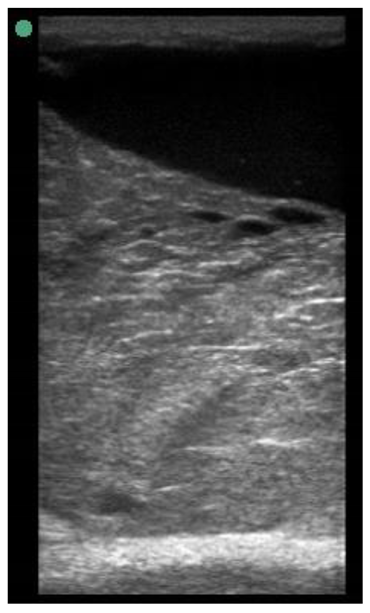

| 113 days of pregnancy (P113) Scanning depth 4.7 cm | ![]() | ![]() | MT generous: 28.9 mm MT conservative: 25.9 mm Gland cistern: 3.3 mm Parenchyma: 10.9 mm Fat Pad: 10.0 mm |